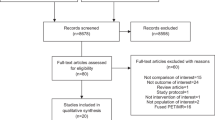

This retrospective review, representing our cumulative experience with a multimodal imaging and detection approach to 18F-FDG-directed surgery for known or suspected malignancies from June 2005 to June 2010 at the Arthur G. James Cancer Hospital and Richard J. Solove Research Institute of The Ohio State University Medical Center (OSUMC), was approved by the OSUMC Cancer Institutional Review Board.

Of those 145 patients, a preoperative patient diagnostic PET/CT scan was done prior to the date of their anticipated 18F-FDG-directed surgery in 90 patients. In the remaining 55 patients, a preoperative patient diagnostic PET/CT scan was done on the same day as the anticipated 18F-FDG-directed surgery. For those 90 patients having their preoperative patient diagnostic PET/CT scan done prior to the day of their anticipated 18F-FDG-directed surgery, mean 18F-FDG injection dose for their prior preoperative patient diagnostic PET/CT scan was 14.3 (± 1.5, range 8.4-16.5) mCi, time from 18F-FDG injection to the preoperative patient diagnostic PET/CT scan was 80.6 (± 18, range 43-179) minutes, and mean duration of time from preoperative patient diagnostic PET/CT scan to the date of the anticipated 18F-FDG-directed surgery was 24 (± 18, range 1-92) days. For those 55 patients undergoing a same-day preoperative patient diagnostic PET/CT scan, mean same-day 18F-FDG injection dose was 16.4 (± 2.4, range 11.7-21.8) mCi and mean time from same-day 18F-FDG injection to their same-day preoperative patient diagnostic PET/CT scan was 73 (± 9, range 53-114) minutes.

Among the 145 patients intravenously injected with 18F-FDG in anticipation for proceeding to the operating room on that same day for surgical exploration, biopsy, and possible resection of a known or suspected malignancy, 142 were eventually taken to surgery on that same day. However, three of the same-day preoperative patient diagnostic PET/CT scans led to the cancellation of the anticipated surgical procedure. In two of these cases, same-day preoperative patient PET/CT scan demonstrated inoperable, widespread metastatic disease. In the other case, there was interval complete resolution of 18F-FDG avidity seen at the time of same-day preoperative patient diagnostic PET/CT scan as compared 18F-FDG avidity seen on a previously performed patient PET/CT scan.